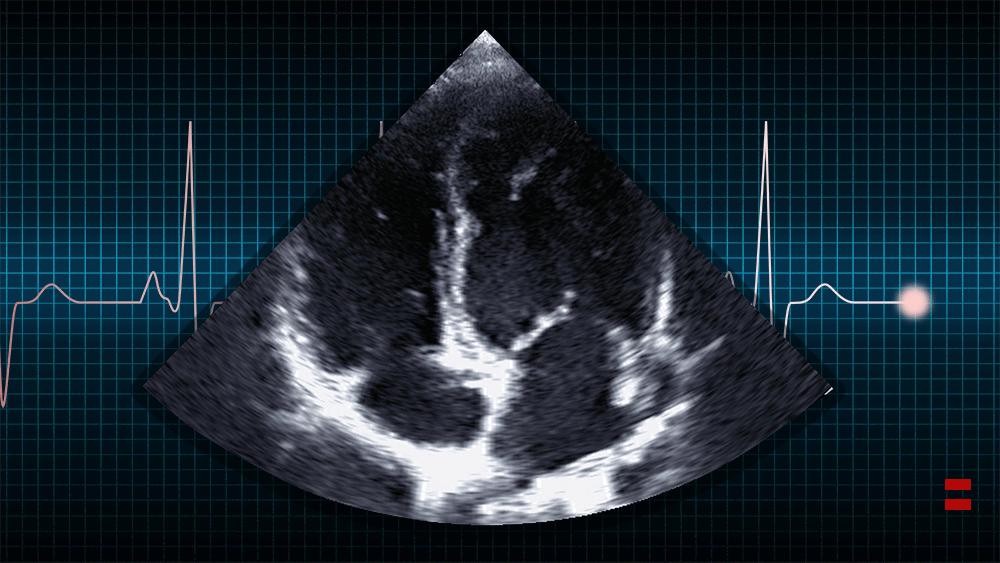

Florence Huang Sheehan ’71 has developed medical ultrasound simulators — and is now training clinicians to monitor Covid-19 patients for heart failure. “From my years at MIT I have the ability to translate between medicine and engineering,” she says. Full story